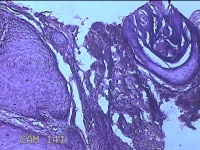

性别

男

年龄

26岁

临床诊断

面部肿物

一般病史

左侧面部无痛性肿物一月余。

标本名称

左侧面部肿物

大体所见

灰白暗红色肿物0.7x0.3x0.2cm一个,表面糜烂。

图1